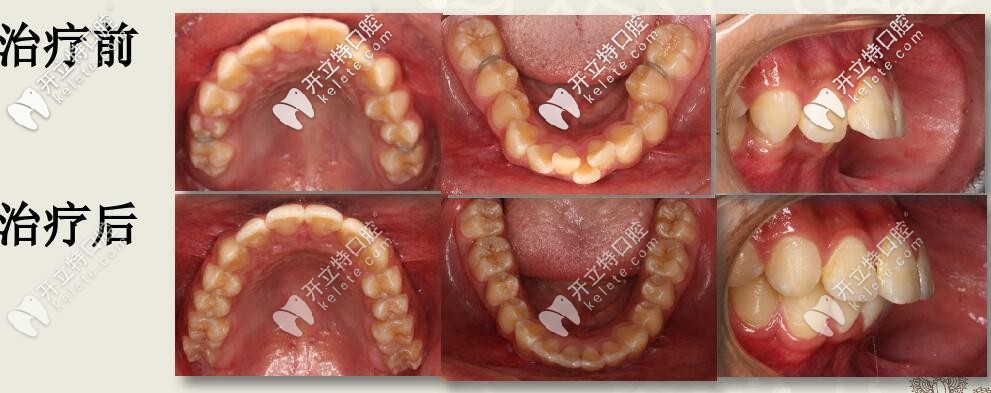

深復(fù)蓋凸嘴伴下巴后縮,直絲弓聯(lián)合擴(kuò)弓,斜導(dǎo)矯正27個(gè)月對比

12歲兒童齙牙,下巴后縮,牙列擁擠,全口直絲弓配合斜導(dǎo)、擴(kuò)弓器以及激動(dòng)器矯治,27個(gè)月后效果驚人。

肉眼可見上前牙唇傾,輕度擁擠 下頜牙弓寬度窄,前牙區(qū)擁擠,后牙去舌傾明顯,前牙深覆蓋,深覆合

I期II期聯(lián)合矯治

1、I期:口外弓抑制上頜發(fā)育,肌激動(dòng)器促進(jìn)下頜發(fā)育

2、II期:全口直絲弓非拔牙矯治,排齊整平上下牙列

3、四眼簧改善下后牙舌傾異常,擴(kuò)弓提供排齊間隙

4、斜導(dǎo)導(dǎo)下頜向前,維持I期前移效果

結(jié)束后,牙列整齊,深復(fù)蓋明顯改善。

本案例,用到了口外弓、肌激動(dòng)器、四眼簧擴(kuò)弓、斜導(dǎo)工具